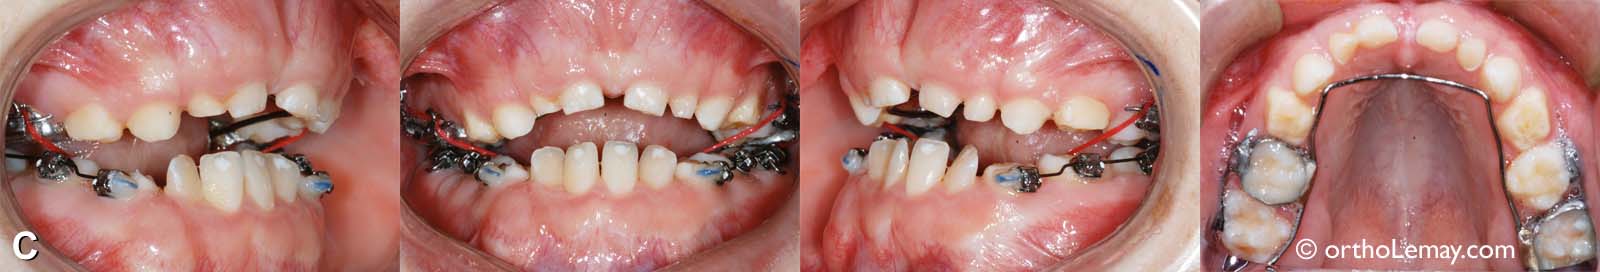

C) Malocclusion

(C) Une fois l’expansion maxillaire complétée, l’appareil d’expansion fut retiré et remplacé par un mainteneur d’espace fixe (fil lingual) pour éviter toute récidive de l’expansion obtenue. La seconde étape consistait en la pose d’appareils multi-bagues fixes (“broches”) dans la région postérieure des deux arcades pour faire de l’expansion dento-alvéolaire à l’arcade inférieure afin de l’harmoniser avec la nouvelle largeur de l’arcade supérieure. Des élastiques en configuration croisée attachés à l’extérieur de l’arcade supérieure et à l’intérieur de l’arcade mandibulaire (visibles en rouge sur les photos) ont permis de déplacer les dents inférieures vers l’extérieur pour élargir l’arcade.